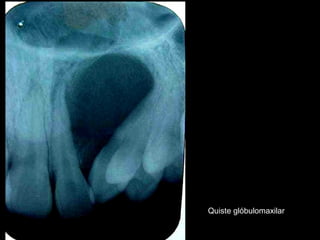

Quiste glóbulomaxilar

Quiste seno maxilar